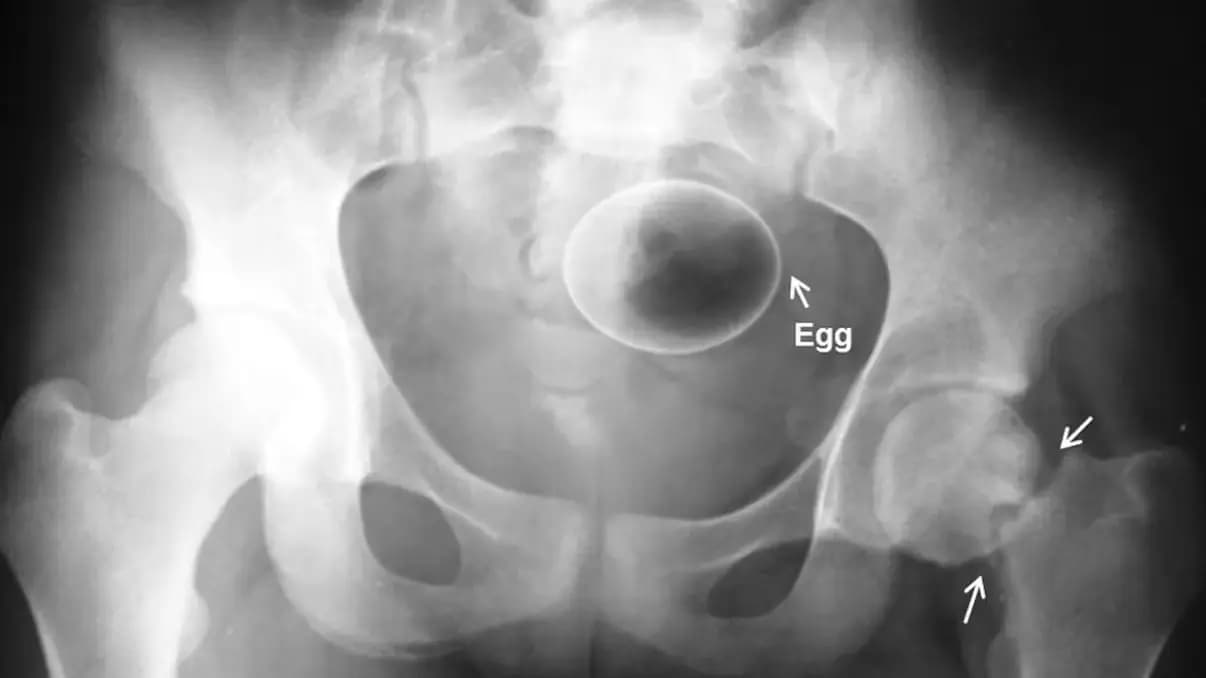

* Яйцо

Фото: Case courtesy of Dr Frank Gaillard, Radiopaedia.or